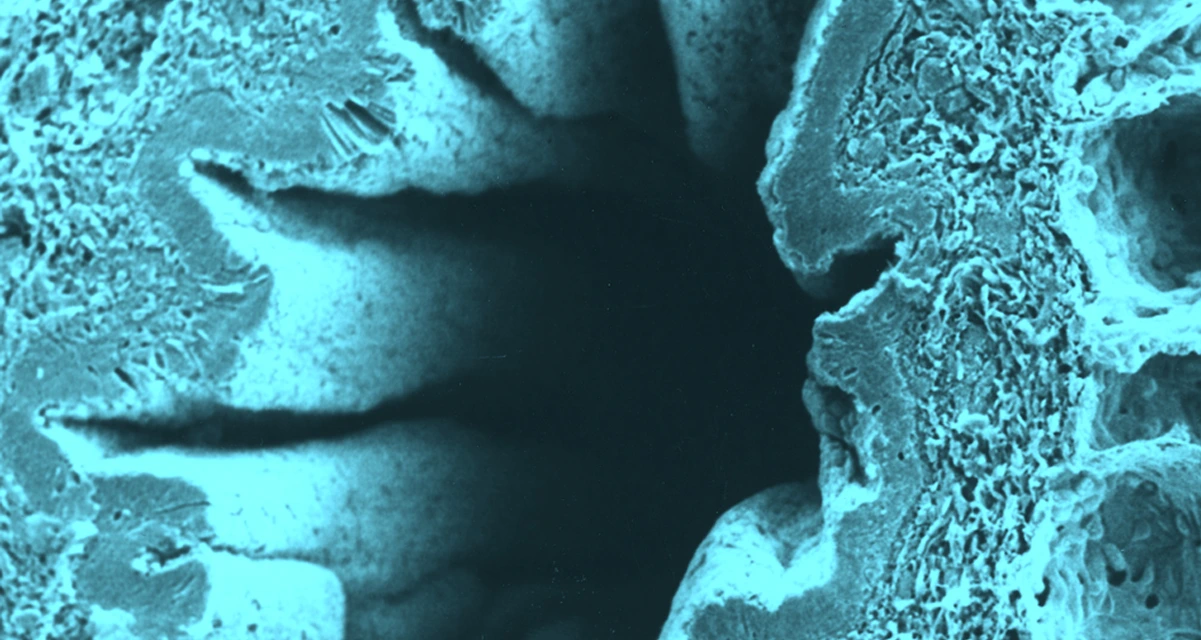

Many environmentally triggered lung diseases are still considered incurable. We explore the immunological mechanisms underlying chronic lung diseases such as COPD, lung fibrosis, asthma, lung cancer and the complications following lung transplantation. We want to translate our findings into preventative and therapeutic approaches for patients.

Many environmentally triggered lung diseases are still considered incurable. We at the Institute of Lung Health and Immunity (LHI) explore the immunological mechanisms underlying chronic lung diseases such as COPD, lung fibrosis, asthma, lung cancer and the complications following lung transplantation. We want to translate our findings into preventative and therapeutic approaches for patients.